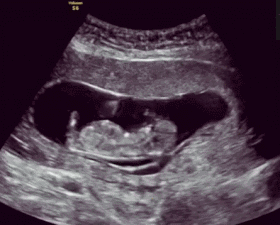

震撼 这些胎动图片你看过吗

你都不好奇宝宝在肚子里干嘛?这22张胎动图,真是萌炸了妈妈的心

胎动真是个很奇妙的感受,看完这20张图,孕妈一定会特别欣慰

越来越强壮,从现在开始,胎儿胎动的频率明显增加,胎动方式也变得多种